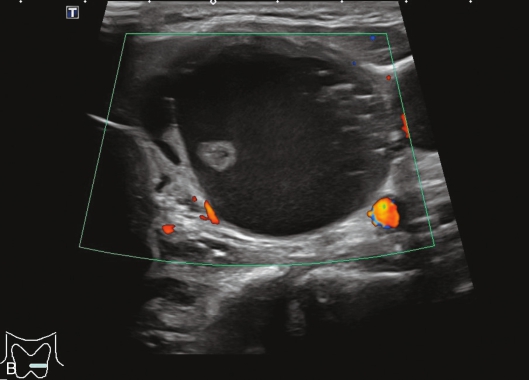

甲状腺囊肿常规超声表现为边界清晰、形态较规则的无回声结节,内可见点状强回声,后伴“彗星尾”征,CDFI内部无明显血流信号,见图1-3-1。

图1-3-1 甲状腺囊肿常规超声声像图

A.甲状腺左叶纵切面;B.CDFI血流图